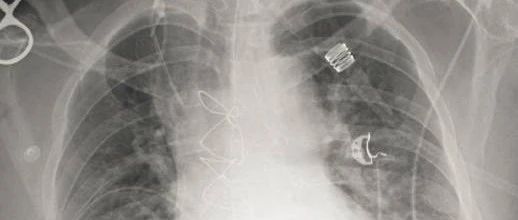

请读题患者,男性,72 岁。既往诊断慢性肺源性心脏病。咳嗽加重伴呼吸困难 2 天。入院后动脉血气显示:pH 7.28,PaO2 56 mmHg,PaCO2 78 mmHg,HCO3- 33 mmol/L。为了纠正该患者的酸碱失衡,答案点击下方空白处获得答案B内容来源:丁香医考 app排版:超超

请听题患者,女性,79 岁。慢性阻塞性肺疾病、肺源性心脏病,以“慢性咳嗽、咳痰 30 年,加重 7 天”为主诉入院。查体:口唇发绀,双肺可闻及干湿啰音。心率 85 次/分,房性早搏,期前收缩 2~3 次/分。答案点击下方空白处获得答案A以上题目和答案解析选自丁香医考呼吸内主治手机题库,你答对了吗?距离 4 月的主治考试越来越近,你有把握一次通过考试了嘛?如果没有,这份题库或许能帮助你更好的备考和通过主治考试!...

DAY 571答案点击下方空白处获得答案ABE慢性支气管炎、肺气肿常见的并发症有自发性气胸、呼吸衰竭、慢性肺源性心脏病(选ABE)。结核病是由结核分枝杆菌引起的慢性传染病,可侵及许多脏器,以肺部结核感染最为常见(C)。肺癌或称原发性支气管癌或原发性支气管肺癌,世界卫生组织(WHO)定义为起源于呼吸上皮细胞(支气管、细支气管和肺泡)的恶性肿瘤,是最常见的肺部原发性恶性肿瘤(D)。